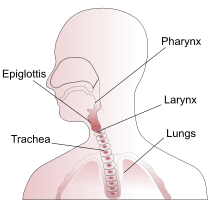

Vector diagram of the human throat. | |

In vertebrate anatomy, the throat (Latin: gula) is the anterior part of the neck, positioned in front of the vertebra. It contains the pharynx and larynx. An important section of it is the epiglottis, which is a flap separating the esophagus from the trachea (windpipe) preventing food and drink being inhaled into the lungs.[1] The throat contains various blood vessels, pharyngeal muscles, the nasopharyngeal tonsil, the tonsils, the palatine uvula, the trachea, the esophagus, and the vocal cords.[2] Mammal throats consist of two bones, the hyoid bone and the clavicle. The "throat" is sometimes thought to be synonymous for the isthmus of the fauces.[3]

It works with the mouth, ears and nose, as well as a number of other parts of the body. Its pharynx is connected to the mouth, allowing speech to occur, and food and liquid to pass down the throat. It is joined to the nose by the nasopharynx at the top of the throat, and to ear by its Eustachian tube.[2] The throat's trachea carries inhaled air to the bronchi of the lungs.[1] The esophagus carries food through the throat to the stomach.[1] Adenoids and tonsils help prevent infection and are composed of lymph tissue. The larynx contains vocal chords,[4] the epiglottis (preventing food/liquid inhalation), and an area known as the subglottic larynx—the narrowest section of the upper part of the throat.[5] In the larynx, the vocal cords consist of two membranes that act according to the pressure of the air.[6]